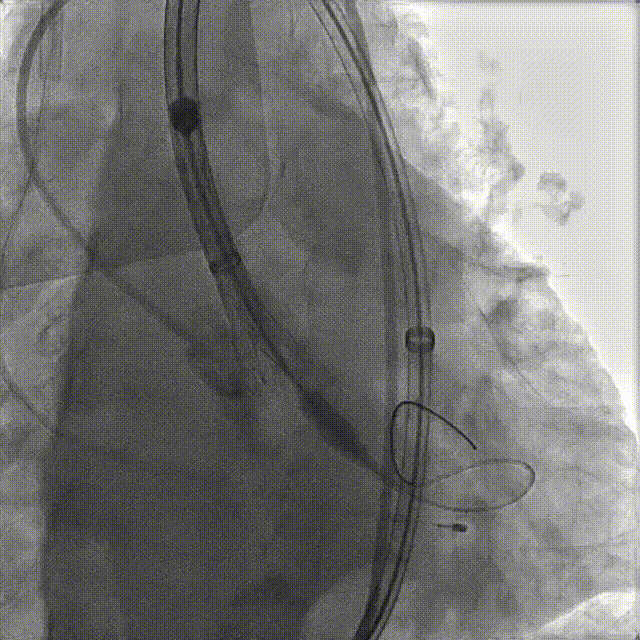

刘煜昊教授 阜外华中心血管病医院(点击查看专家详细简历) 首瓣选耐久,干瓣护航全生命周期管理 2025年ESC专家共识里指出:“推荐第一个瓣膜要选经证实具有长期耐用性的外科瓣膜与经导管瓣膜,以降低再次介入治疗的可能性 ,对于瓣环较小、根据预测有效瓣口面积(EOA)评估存在严重 PPM 风险的患者,可采用主动脉根部扩大术联合 SAVR,或植入环上瓣,对于小瓣环患者自展瓣拥有比较好的血流动力学优势”。 每一次术前评估,都是我们与患者携手面对未知的起点。我们始终以患者全生命周期获益为核心,在瓣膜选择与术式规划中,不只着眼于当下解剖适配,综合评估解剖条件、预期寿命与生活质量。从年轻患者到高龄人群,瓣膜耐久性与血流动力学稳定性始终是决策核心! 陈同峰教授 阜外华中心血管病医院(点击查看专家详细简历) 医学的进步正不断拓宽生命的边界,每一次术前评估都是对生命尊严的深度凝视,技术与人文的交融,让风险不再仅是数字的堆叠,而是成为医者与患者共同面对未知的勇气见证。术中瓣膜释放结束,到了导管测压的时候,我惊喜:瓣膜不错啊,压差为0,这不仅仅得益于瓣膜形态的设计,更是环上瓣及瓣叶材质优质的体现,感受到了 Prostyle A瓣膜在血流动力学上的卓越表现,其采用的抗钙化处理技术有效延长了瓣膜的耐久性,为患者长期生存提供了更可靠的保障。 患者病史 主诉:心慌半月; 门急诊诊断:心悸,冠状动脉粥样硬化性心脏病,心脏瓣膜病,主动脉瓣狭窄,高血压,甲状腺术后; 现病史:半月前无明显诱因出现心慌,呈间断性,伴心悸、出汗,伴头晕,无咳嗽、咳痰,无恶心、呕吐,无双下肢水肿,无放射痛及意识障碍,休息约几分钟后可自行缓解,症状反复发作,遂来我院就诊。 术前超声提示:室间隔增厚;主动脉瓣退行性变并重度狭窄;升主动脉明显增宽;室间隔增厚。 术前CT 三叶瓣,轻度钙化集中在无窦和左窦瓣叶边缘,主动脉根部直径19.3mm,LVOT直径17.7mm,LVOT向下收窄; 窦部正常,VTC空间足够,冠脉风险低; 左室腔小,收缩末径20-25mm,“自杀左室”,循环崩溃风险高;主动脉瓣环水平夹角71.1°,横位心,过弓和跨瓣存在一定困难,备snare。 外周双侧入路内径可,双侧入路能够支持20F大鞘通过,右股低分叉。 手术策略 推荐右侧股动脉为主入路,左侧为辅助入路,右股分叉上方1cm穿刺;推荐选择AV23瓣膜,18mm球囊预扩,左右重叠位:LAO 7° CAU 35°;左冠切线位:LAO 27° CRA 16°;右窦居中位:LAO 18° CAU 9°;备Snare,建议ECMO/CPB湿备,术前术中积极补液,警惕循环崩溃风险。 手术过程 在右股动脉穿刺建立通路后,顺利送入大鞘,经食道超声及血管造影确认路径稳定。18mm球囊预扩过程中,患者血压一度下降,迅速完成扩张并立即植入AV23 ProStyle A®瓣膜。瓣膜精准释放于目标位置,超声显示无明显反流及瓣周漏,血流动力学即刻改善。 主动脉根部造影 18mm球囊预扩少量反流 输送系统柔顺跨瓣 精准定位 平稳释放 80%工作位观索位置合适 释放后导管测压,压差由术前53mmHg降为0mmHg 最终造影瓣膜位置形态良好,冠脉灌注良好,无明显瓣周漏 ProStyle A®预装干瓣——助力临床最优化解决方案: 轻松过弓,精准可控:该病例为横位心,在未使用snare的情况下,过弓和跨瓣柔顺,较细的尺寸+柔顺的输送系统通过性能得到了很好的验证; 平衡的收腰设计:该病例瓣环较小且左室腔小,AV23瓣膜的平衡收腰设计既确保了锚定安全性,又保证了EOA,有效降低了循环崩溃风险,而术后0mmHg的压差的表现更加证明了优秀的血流动力学,提高了瓣膜的耐久性; 预装干瓣 便捷顺安:金仕生物专利抗钙化技术运用纳米技术去除组织内的细胞碎片和磷脂,封闭游离醛基,从根本上阻断了瓣膜钙化的多项因素,显著提升了瓣膜的耐久性;同时,相比较传统戊二醛保存方式,干式存储最大限度的保留心包的亲水亲油平衡,还原组织天然曲柔性,进一步保障了瓣叶开合,保证长期耐久性。 专家简介 王小虎 阜外华中心血管病医院(点击查看专家详细简历) 陈冲 阜外华中心血管病医院(点击查看专家详细简历) 赵一品 阜外华中心血管病医院(点击查看专家详细简历)